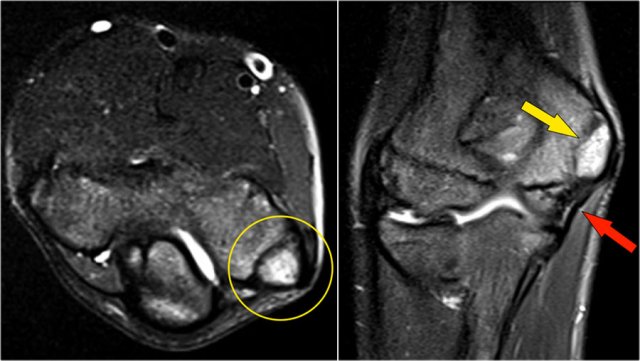

Coronal view:

1. Lateral collateral ligament is completely stripped (yellow arrow).

2. radial head is subluxed.

3. marrow edema of the coronoid process due to the fracture (red arrow).

Sagittal view:

1. Radial head is a little bit subluxed posteriorly (yellow arrow).

2. Large effusion and capsular disruption posteriorly.

3. Contusion of the posterior side of the capitellum as a result of impaction by the coronoid process (red arrow).

All these signs are the result of a posterior dislocation.